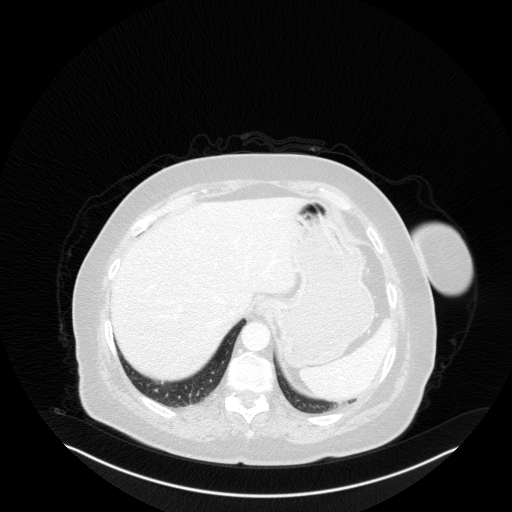

Image Grid

4Γ—3 grid: Rows show different image types (Original NATIVE, Reconstructed NATIVE, Original VENOUS, Generated VENOUS), Columns show windowing techniques (No Window, Lung Window, Mediastinum Window)

Reconstructed NATIVE CT scan (cycle consistency)

Full window (WL 1023.5, WW 4095 β†’ Low βˆ’1024, High +3071)